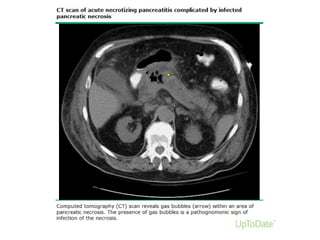

Infected pancreatic necrosisInfected pancreatic necrosis

• Necrosis is variable, may remain solid or liquefy, remain sterile or

become infected, persist, or disappear over time.

• occurs > the first week.

• Infected pancreatic necrosis is important because of the need for

antibiotic treatment and likely active intervention.

• The presence of infection - extraluminal gas in the pancreatic and/or

peripancreatic tissues on CECT or PFNA is positive for bacteria and/or

fungi on Gram stain and culture.

• There may be suppuration (pus) associated with the infected

pancreatic necrosis, leading to liquefaction – abscess

A 47-year-old man with acute necrotising pancreatitis complicated by infected pancreatic

necrosis.

Banks P A et al. Gut 2013;62:102-111

Copyright © BMJ Publishing Group Ltd & British Society of Gastroenterology. All rights reserved.